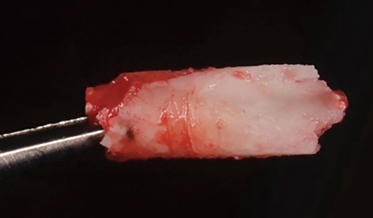

- Improving the Prognosis of Periodontally Involved Teeth at the Time of Extraction of Adjacent Teeth With an Amnion-Chorion Barrier and Bioactive Dentin Graft